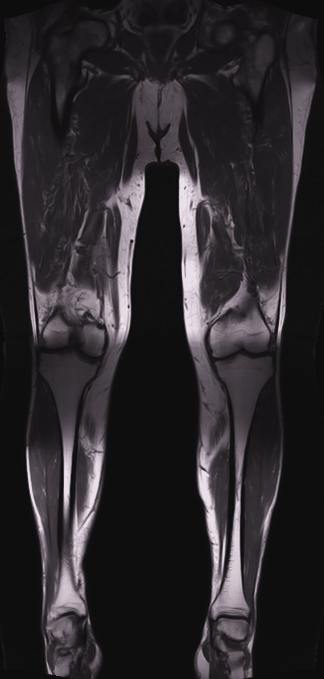

La Resonancia magnética (RMN) es un método de imagen multiplanar no invasivo, basado en la interacción entre la radiofrecuencia, los campos magnéticos y ciertos núcleos en el cuerpo humano (generalmente núcleos de hidrógeno del agua), después que el cuerpo ha sido introducido en un campo magnético fuerte. La información obtenida es procesada por un ordenador y transformada en imágenes del cuerpo humano.

La RM consigue información sobre la estructura del cuerpo permitiendo diferenciar entre tejidos normales y anormales lo que la convierte en una técnica muy sensible para detectar enfermedad. Esta sensibilidad está basada en un alto grado de contraste debido a las variaciones en las propiedades de relajación magnética de los diferentes tejidos, tanto normales como anormales.